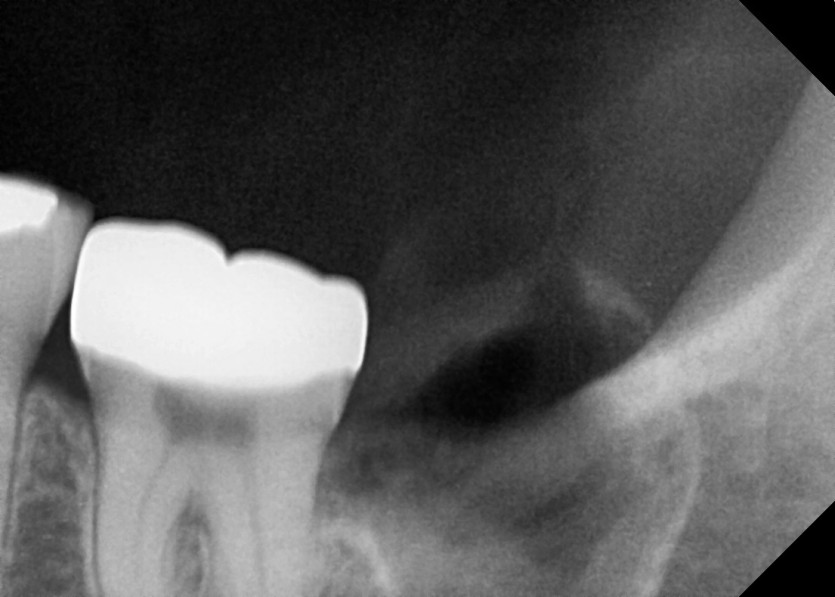

#38 사랑니 발치

구강 외과 전문의가 당일 발치했습니다.